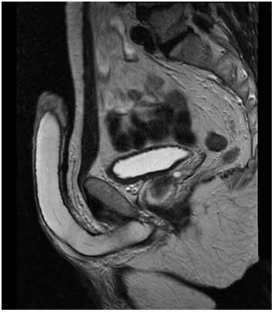

This article provides an overview of the current concepts in reconstructive surgery following penile trauma, penile fracture and penile cancer. It covers the initial management of penile trauma, with the aim of preservation of as much viable tissue as is practical, and also provides advice on dealing with penile avulsion and amputation injuries. The best treatment for penile fracture—immediate surgical exploration and repair—is outlined and discussed. Finally, penile cancer management is reviewed, from initial biopsy to definitive treatment of the penile lesion—including wide excision, partial glansectomy, total glansectomy, and partial and total penectomy. It is concluded that appropriate surgery in all these conditions reduces subsequent long-term problems in sexual function, cosmesis, psychology, and (in cancer cases) longevity. The same reconstructive techniques can be applied for different penile conditions, and it is suggested that surgeons become experienced in genital surgery as a whole, rather than in oncology or trauma alone.